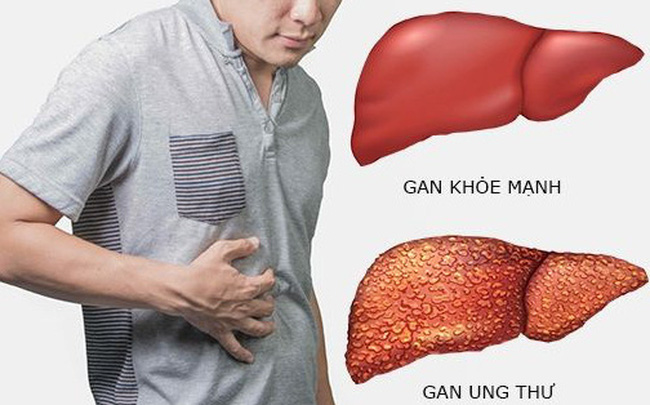

Triệu chứng ung thư gan

Một trong những khó khăn trong việc phát hiện ung thư gan là các triệu chứng ban đầu thường không rõ ràng. Nhiều trường hợp chỉ được phát hiện khi bệnh đã ở giai đoạn muộn.

Một số biểu hiện có thể gặp ở người bệnh bao gồm:

- Đau tức vùng gan kéo dài

- Chán ăn, mệt mỏi

- Sụt cân nhanh không rõ nguyên nhân

- Sốt nhẹ kéo dài

- Vàng da nhẹ do suy giảm chức năng gan hoặc tắc mật

Khi khám lâm sàng, bác sĩ có thể phát hiện gan to, bề mặt gan không đều hoặc có khối u phát triển nhanh.

Ở giai đoạn muộn, người bệnh có thể xuất hiện các biến chứng như cổ trướng, lách to, tuần hoàn bàng hệ hoặc vàng da rõ rệt.

Ung thư gan thường có tiên lượng khá nặng nếu không được phát hiện sớm. Bệnh có thể gây ra nhiều biến chứng nghiêm trọng như cổ trướng ung thư, xuất huyết tiêu hóa, chèn ép đường mật hoặc vỡ khối u. Ngoài ra, ung thư gan còn có khả năng di căn đến nhiều cơ quan khác trong cơ thể như phổi, màng phổi, xương, hạch bạch huyết hoặc não. Chính vì vậy, việc phát hiện sớm đóng vai trò rất quan trọng trong việc nâng cao hiệu quả điều trị.